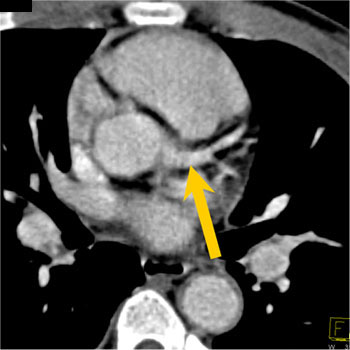

Aneurysm of Circumflex Coronary Artery 27 year old female with symptoms of increasing fatigue and pulsation in the left chest and neck. CTA demonstrates a persistent left SVC and aneurysm of the circumflex coronary artery.

Dx-Aneurysm of the Circumflex Coronary Artery In this patient the cause of the coronary artery aneurysm was atherosclerotic disease and could best be managed by surgical intervention. The patient ultimately decided against any intervention.